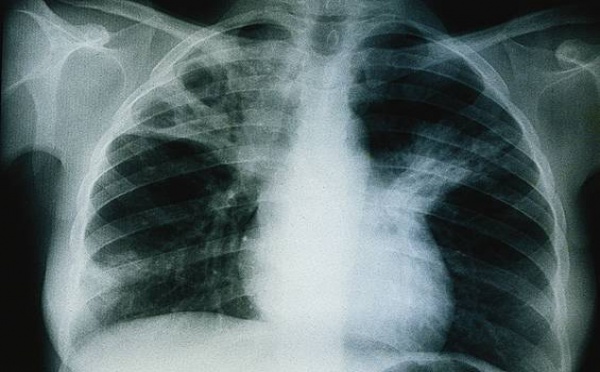

Tuberculose à Thiès : 500 nouveaux cas attendus en 2012

« A Thiès 400 ou 500 cas de tuberculose sont attendus chaque année », la déclaration est d’Amadou Djigal du Programme national de lutte contre la tuberculose. Déjà la Région Médicale a dépisté 62% de potentiels vecteurs de la maladie, dans ce lot 85% de ces malades sont totalement guéris. Malheureusement dans le lot des...